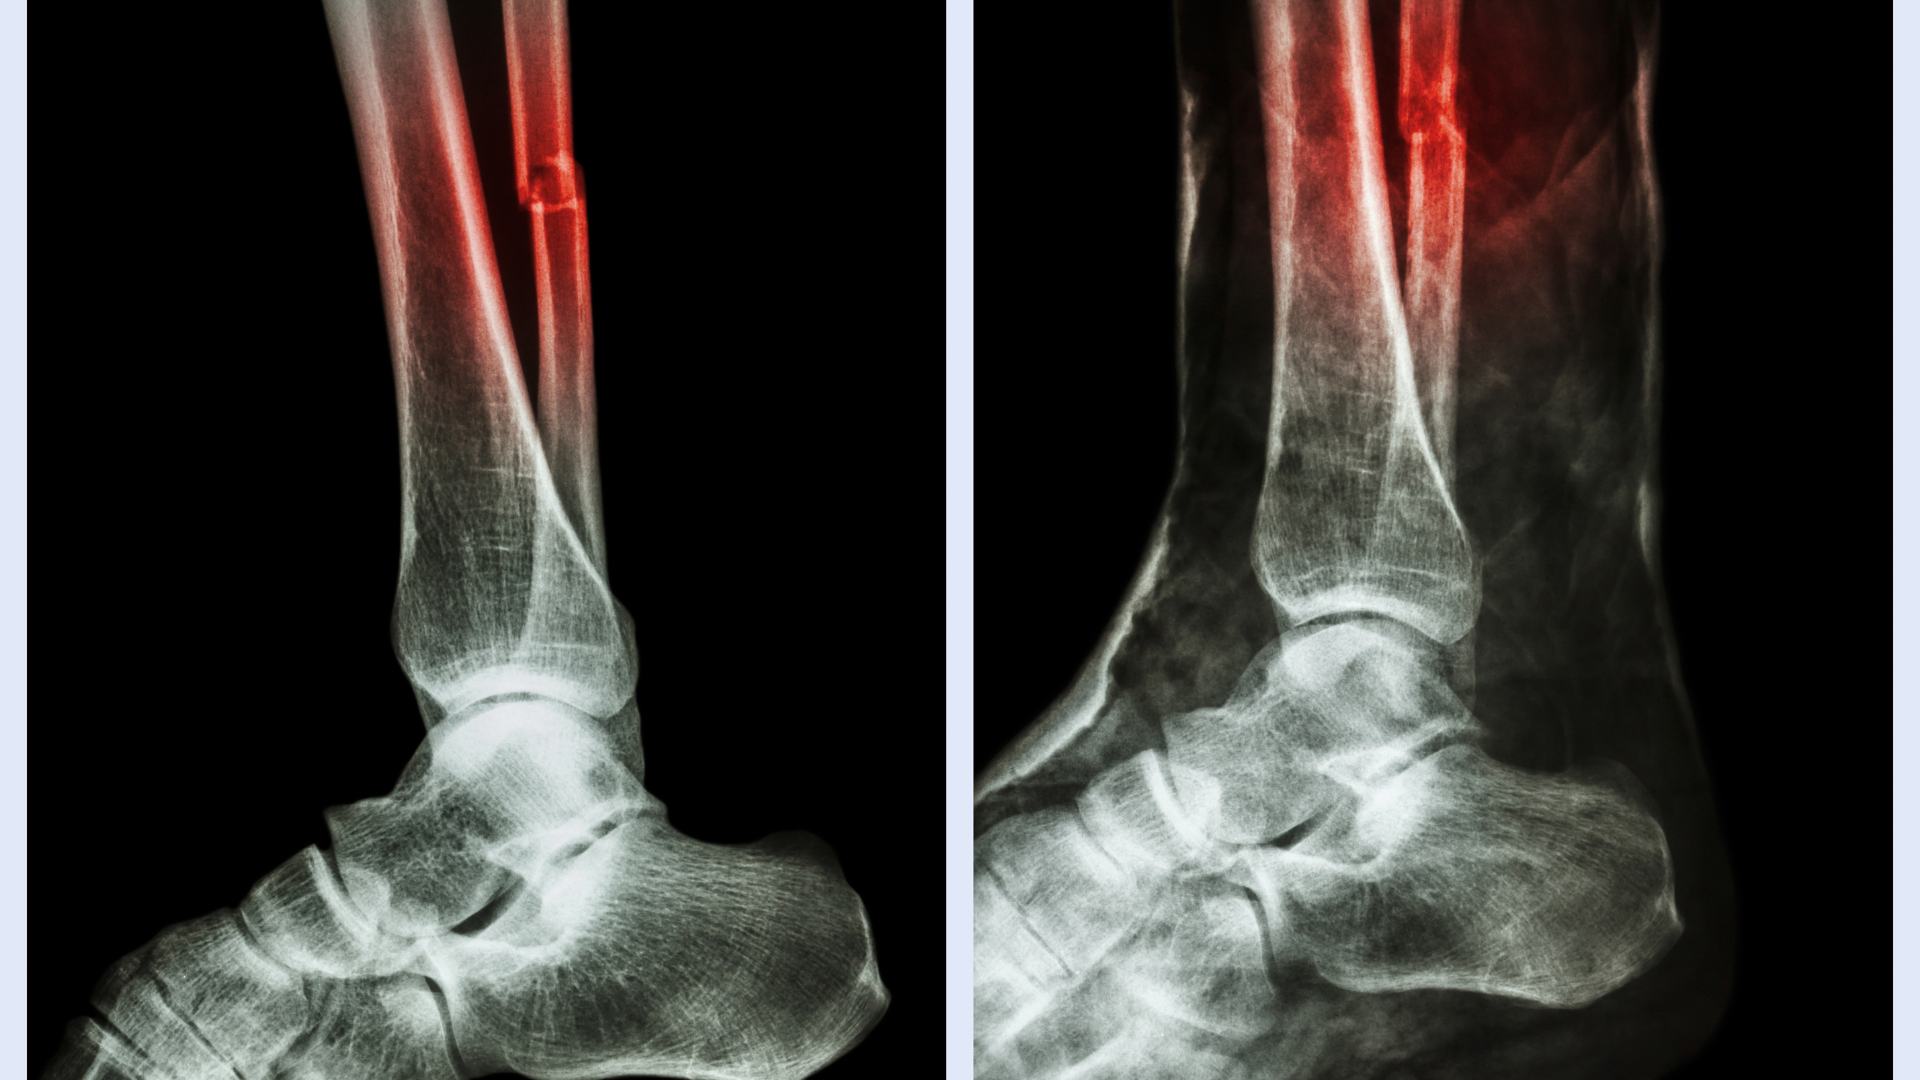

Chẩn đoán hình ảnh giúp xác định vị trí và mức độ gãy. X-quang cẳng chân là bước cơ bản, trong khi CT scan hoặc MRI được sử dụng khi nghi ngờ gãy phức tạp hoặc tổn thương mô mềm, giúp bác sĩ đưa ra phương án điều trị chính xác.